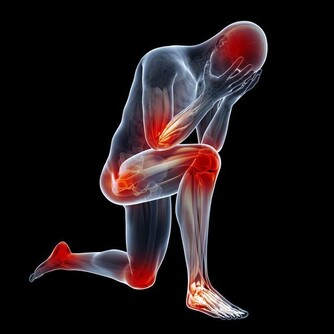

三、為何運動能紓解腰痛?

腰痛常與核心肌群無力有關。透過運動加強腹肌、背肌與骨盆底肌肉的力量,能穩定脊椎並減輕腰椎負擔。

促進軟組織修復

運動能刺激肌肉與關節周圍軟組織的新陳代謝,促進受損組織修復,同時增加關節靈活度,減少僵硬與疼痛感。